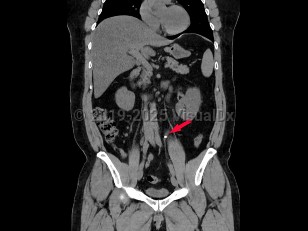

AscariasisAscariasis

Ureteral calculus